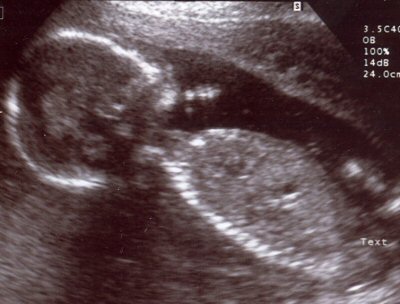

Above is a hospital sonogram image of a human child in its mother's womb soon to be born.